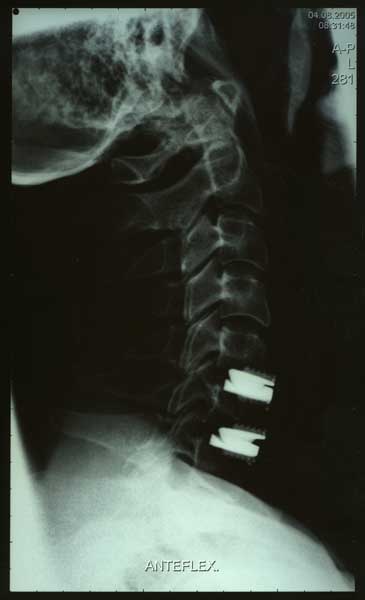

Bild 1 - 4 von links nach rechts

Bild mit Prestige-Prothese

monosegmentale Versorgung

bisegmentaler Versorgung - Anteflexion